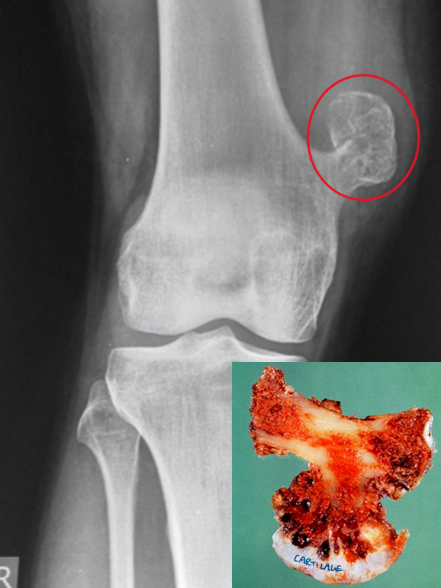

osteochondroma

benign outgrowth (exostosis) of bone with a cartilage cap

develop only in bones of endochondral origin & arise from the metaphysis near the growth plate of long tubular bones → especially near the knee

grossly seen as mushroom-shaped outgrowths

only bone portion seen on X-ray

MEN affected more than women

late adolescence & early adulthood

may be associated with an increased risk of malignancy (5 - 20% of hereditary type)